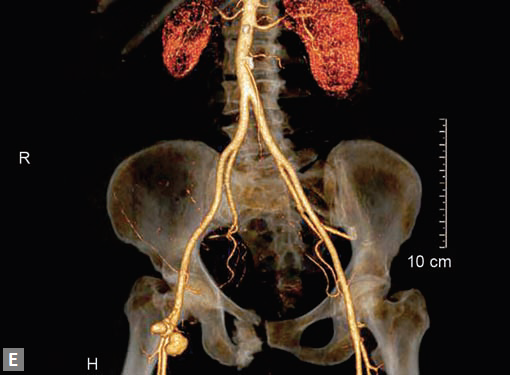

Pseudoaneurysms at femoral access site, arterial grafts are best assessed by CT (Figs 25E to I).

Along with IVC, relationship of iliac veins and artery is assessed. May-Thurner syndrome occurs when left common iliac vein is compressed between the right common iliac artery and the vertebral body. Reverse May-Thurner syndrome occurs in situs inversus abdominus associated with heterotaxy syndromes.

Aneurysms occur in IVC rarely. Gradman and Steinberg have classified IVC aneurysms25 (Fig. 26) into four types. Type 1 involves suprahepatic IVC and there is no IVC obstruction associated. Type 2 is associated with supra- or infrahepatic caval interruption. Type 3 involves infrarenal IVC and there is no associated congenital anomaly. Type 4 involves iliac veins and usually a left IVC is seen. Like elsewhere, aneurysm can be saccular or fusiform, shape wise.

An interesting fistula between iliac artery and vein can occur following a lumbar disk surgery. Patient generally presents with unilateral slow onset lower limb swelling and generally a bruit can be heard in lower abdomen/pelvis.

In general assessment of lower limb venous system is not adequate in CT. An AV fistula following a femoral puncture is one common scenario a radiologist comes across. Enhancement of venous structures in early arterial phase including IVC is the first clue. A track between the artery and a vein is generally well seen by the radiologist. Venous malformation is seen as diffuse hypodensity with cystic spaces in soft tissues of upper limb or lower limb. A faint contrast enhancement in delayed scan, characteristic of a low-flow malformation is seen. Enhancement of septa is suggestive of lymphatic malformation and mixed occurrence is not infrequent. In AV malformation, feeder arteries and draining veins are seen. Arteries generally are hypertrophied.